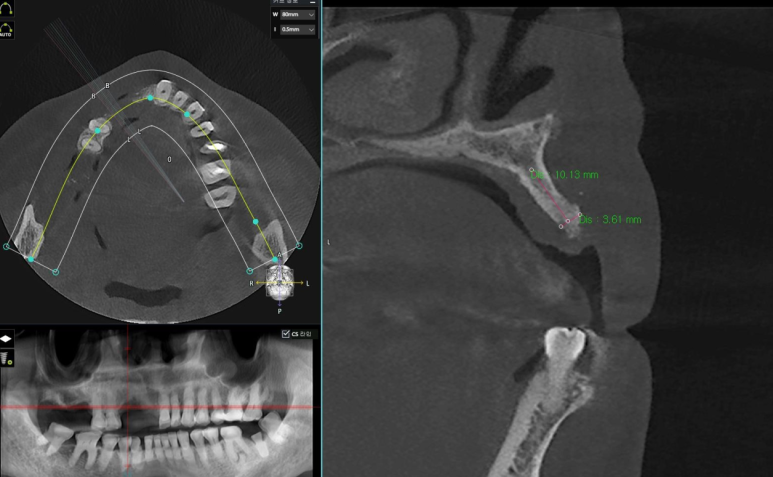

우선 첫 과정으로 3D 구강스캔과 CT 촬영을 하는데요.

그 이유는 직접적인 절개를 하지 않고 잇몸과 치아 상태를 3차원 데이터로 파악하려는 목적입니다.

이렇게 얻은 3차원 데이터는 모의수술(시뮬레이션)도 진행할 수 있는데요.

모의수술 과정에서 정확히 어디에 식립을 할지, 깊이와 위치까지 계산하게 됩니다.

잇몸을 직접 열지 않고도 어디에 식립하면 좋을지 확인할 수 있는 것이죠.

잇몸이 3mm정도로 얇은 분